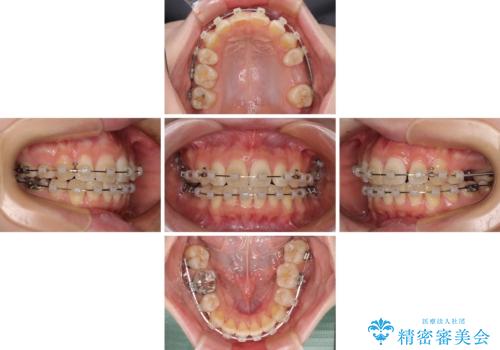

マウスピース矯正でもワイヤー矯正後でも対応可能でしたが、自己管理の煩わしさからワイヤー矯正後を選択されました。

舌のトレーニングをしっかりと行っていただきながらワイヤー装置により矯正治療を行い、途中でインプラントを埋入し、矯正治療後に補綴治療を行うこととしました。